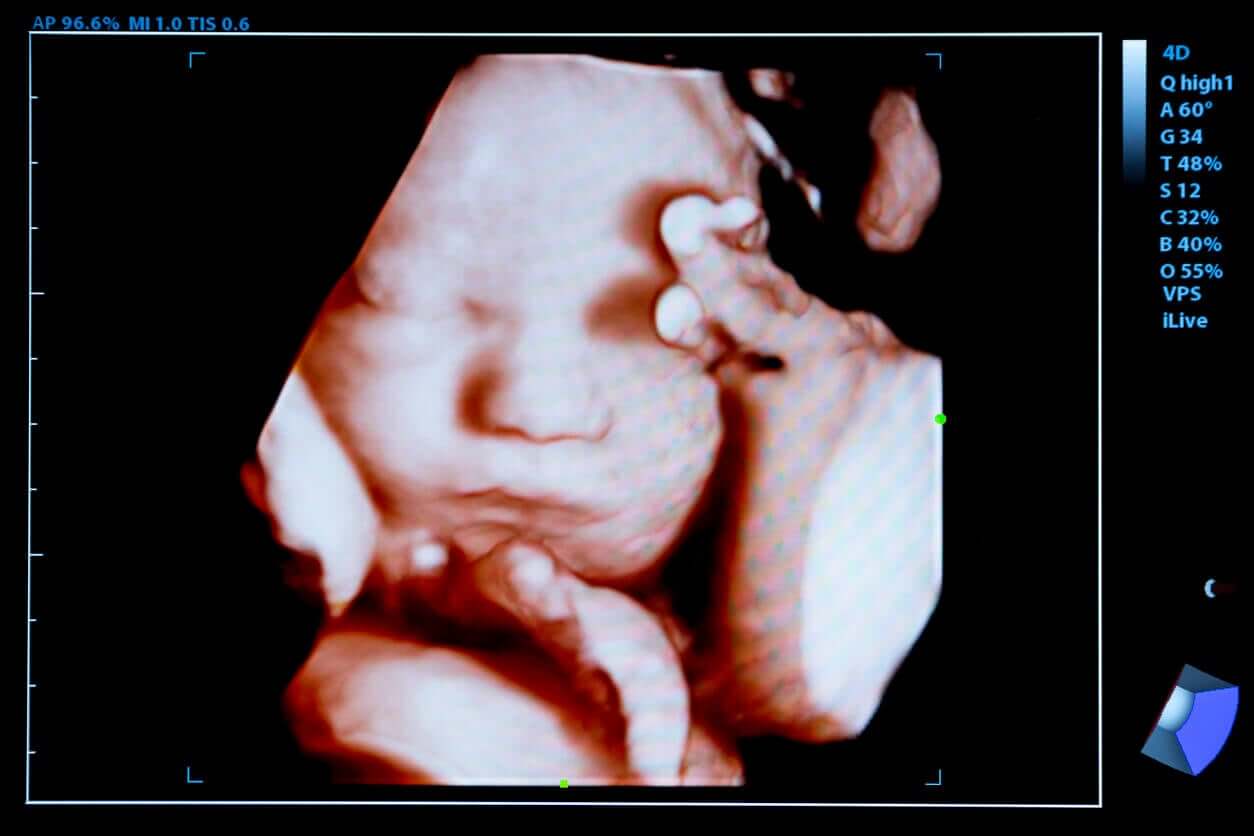

4D-echografie is een nieuwe diagnostische test waarmee gedetailleerde beelden van de foetus verkregen kunnen worden door middel van hoogfrequente ultrageluidsgolven. In tegenstelling tot de vorige lukt het om in één seconde ongeveer 24 beelden te reproduceren en ze beweging te geven.

Naast een gedetailleerd onderzoek van het lichaam van het kind kan men dan verschillende bewegingen zien die het kind maakt, zoals glimlachen, duimzuigen of geeuwen.